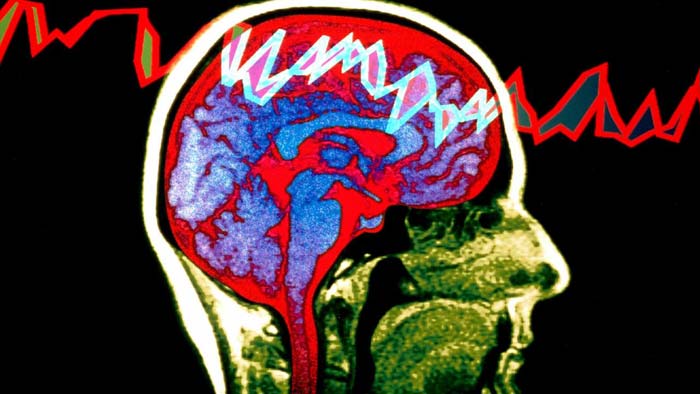

درمان بیماری صرع

داروهای ضد صرع یا AEDsها فعالیت الکتریکی مغز را که باعث تشنج میشود، کنترل میکنند. در صورتی که این داروها به صورت منظم و در ساعات مشخصی در روز مصرف شوند میتوانند بهترین نتیجه را داشته باشند. طبق آمار گرفته شده حدود هفتاد درصد از افرادی که از این داروها استفاده میکنند تشنج را به طور کلی تحت کنترل درآورده اند. اما باید بدانید که این داروها نمیتوانند صرع را درمان کنند و یا نمیتوانند هنگام روی دادن تشنج جلوی بروز آن را بگیرند. هدفی که در استفاده از این داروها دنبال میشود، استفاده از کمترین مقدار و تعداد داروهای ضد صرع با کمترین اثرات جانبی برای متوقف کردن تمام تشنجهاست.هنگام درمان بیماری صرع با دارو، پزشک ابتدا از یک داروی ضد صرع و در کمترین مقدار شروع به درمان میکند و به تدریج و تا زمان رسیدن به کنترل تشنجها در بیمار مقدار آن را بالا میبرد. در صورتی که این دارو جواب ندهد و با مصرف آن تشنجهای فرد کنترل نشود، یک داروی ضد صرع جدید اضافه میشود و داروی قدیمی به آرامی کنار گذاشته میشود.

جراحی که برای توقف تشنجهای ناشی از بیماری صرع یا کاهش آنها انجام میشود یکی از انواع جراحیهای مغز به شمار میرود. جراحی صرع انواع مختلفی دارد. یک نوع این جراحیها به این صورت است که قسمت خاصی از مغز که تصور میشود مسبب بروز تشنجهاست، حذف میشود. در نوع دیگر، ارتباط آن بخشهایی از مغز که باعث بروز تشنج میشوند را از سایر قسمتهای مغز جدا میکنند. برای پیدا کردن این نقاط قبل از عمل از فرد آزمایشهایی از جمله اسکن MRI، الکتروانسفالوگرافی (EEG) و دور سنجی ویدئویی گرفته میشود. این روش در برخی افراد شدت تشنجها را کاهش میدهد و در برخی دیگر تعداد آنها را کم میکند.۵- تحریک مغز به صورت عمیق